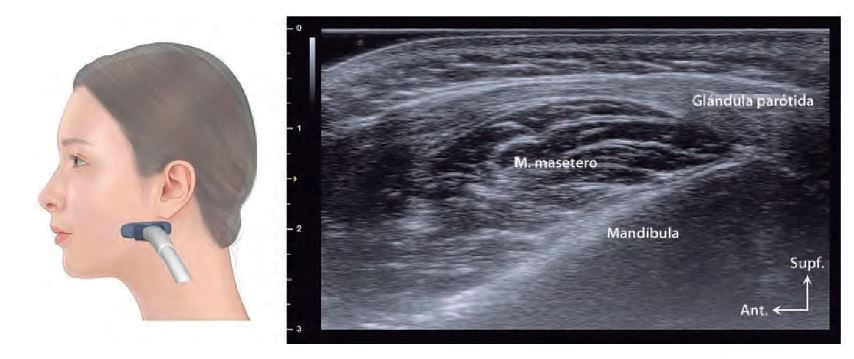

El conocimiento del grosor de la piel, que varía entre regiones como el párpado superior (0,38–0,80 mm) y la punta nasal (1,22–2,01 mm), es fundamental para ajustar técnicas de inyección y procedimientos quirúrgicos. Además, la localización precisa de glándulas salivales (parótida, submandibular y sublingual) mediante ecografía evita complicaciones durante intervenciones en la región mandibular y cervical.